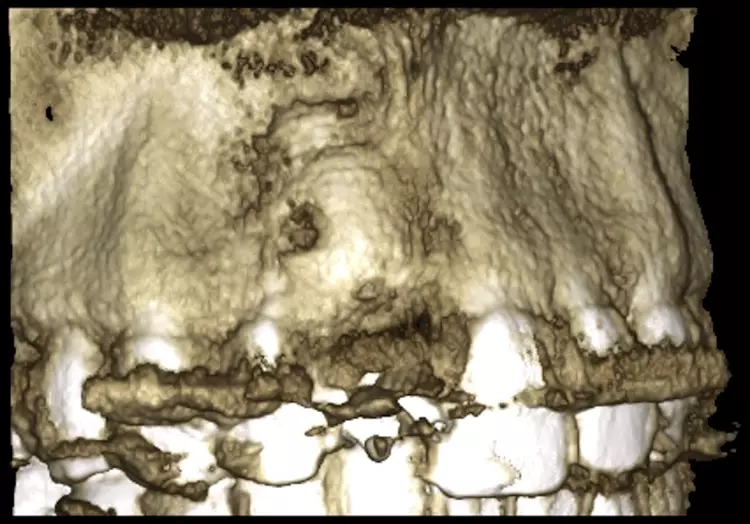

Im Sinne eines Backwardplanning wurde anhand eines Waxups die Marylandbrücke als auch die entsprechende Bohrschablone hergestellt. Nach eingehender präimplantologischer Diagnostik mittels Modellanalyse und digitalem Volumentomogramm (DVT) zeigte sich eine ausgeprägte bukkale knöcherne Fenestration (Abb. 8 und 10).

In einem zweizeitigen Vorgehen wurde der Defekt im Sonic Weld Rx-Verfahren mittels Eigenknochen und BioOss (Geistlich, Wolhusen, Schweiz) im Verhältnis 1:3 augmentiert. Der autologe Knochen wurde über der Defektregion paranasal mittels Trepan gewonnen und mit BioOss gemischt. Um die ursprüngliche Kontur des Alveolarfortsatzes mit dem charakteristischen Jugum alveolare wiederherzustellen, kam der entsprechend vorgeformte Alveolenprotektor zur Anwendung.

Nach einer viermonatigen Einheilzeit wurde im Rahmen der präimplantologischen Diagnostik ein DVT zur Überprüfung des Augmentationsergebnisses erstellt und die Implantatgröße festgelegt (Abb. 9 und 11). In Lokalanästhesie und unter Zuhilfenahme einer Bohrschablone erfolgte nach midkrestaler Schnittführung unter Schonung der Papillen die manuelle Insertion eines Straumann Bone Level Implantats mit den Maßen 4,1 x 10 mm RC (Straumann AG, Basel, Schweiz). Das Eindrehmoment betrug 35 Ncm.